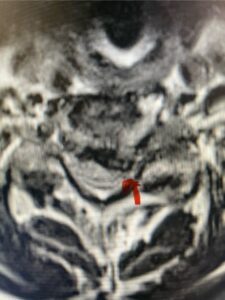

In this next case, this patient is a 47 year-old female who presents with intractable low back pain with severe pain, numbness, and weakness in the right lower extremity that had gotten progressively worse over a year. The patient had failed conservative management including physical therapy and epidurals. She was noted to have ⅘ weakness of plantar flexion. MRI demonstrated a large right L5-S1 disc herniation with severe compression of the descending right S1 nerve root (Fig 3). It was decided to perform a right L5-S1 hemilaminectomy for removal of the disc fragment and decompress the S1 nerve root. When you expose the disc, one must be certain to release any anterior adhesions to the nerve root in order to prevent a dural tear during retraction of the nerve root. It is also important to make sure during exposure and you finally encounter the dura after removing the ligamentum and fat, to make sure you are looking at the nerve root and not the main trunk of the thecal sac because if you don’t you can avulse or damage the nerve root if you retract the wrong structure.

Fig. 3a: Sagittal and axial T2-weighted lumbar MRI images demonstrating large right L5-S1 disc herniation (red arrows)